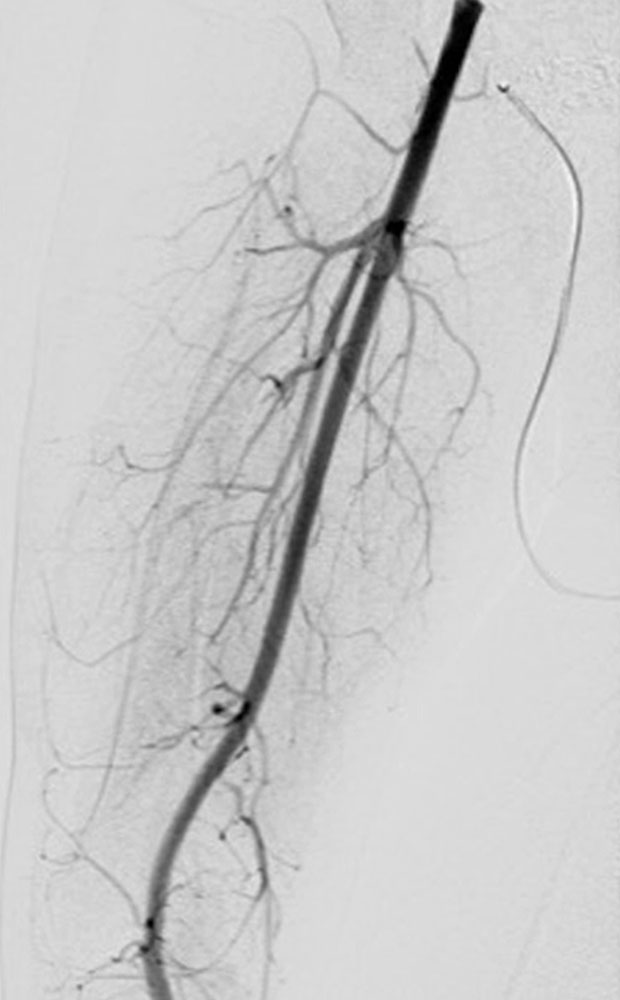

Mikrofistulöse-AVM/-AVF sind außer in der Subkutis ausgedehnt auch in der Muskulatur und im Knochen zu finden.

• Embolisation von arteriovenösen Fisteln (bei Komplikationen oder lokal vor Epiphyseodese)